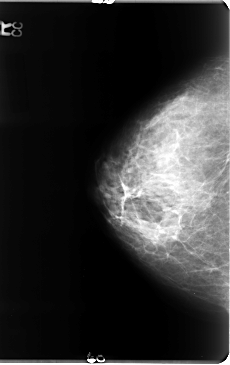

B_3072_1.RIGHT_MLO

RIGHT_CC LINES 4744 PIXELS_PER_LINE 2984 BITS_PER_PIXEL 12 RESOLUTION 50 NON_OVERLAY

RIGHT_MLO LINES 4672 PIXELS_PER_LINE 2872 BITS_PER_PIXEL 12 RESOLUTION 50 NON_OVERLAY